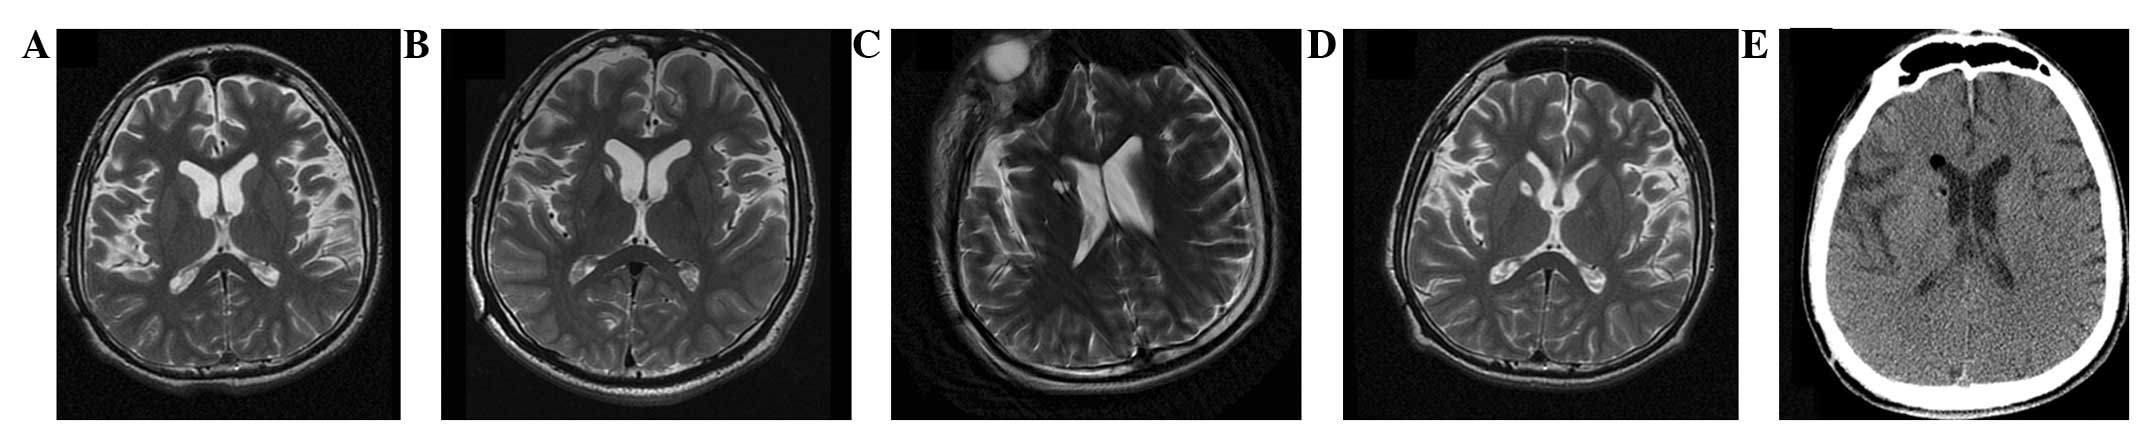

(A) 術前 MRI 顯示腦萎縮。 (BD)術后1年、3年、4年MRI與術前MRI相比無明顯變化。 (E) 術后3天,計算機斷層掃描顯示沒有出血或水腫。

本研究選擇的患者為18歲男性,患有PTD,預產期剖宮產出生,無任何遺傳病家族史,無腦炎、黃疸、腦腫瘤病史或外傷。他在5歲時首次出現左下肢不自主痙攣和扭轉,沒有任何誘發因素。臨床特征從5歲至9歲逐漸擴展到全身。18歲時,患者無法書寫、抓握、站立或行走。他吞咽固體食物有些困難,但沒有癲癇癥狀。患者智力正常。頭部計算機斷層掃描(CT;圖1a)和磁共振成像(MRI;圖2a)提示大腦輕度萎縮。PTD是根據上述數據診斷的。

CT(圖1b-e)和MRI(圖2b-d)掃描顯示4年隨訪期間沒有顯著變化。 手術前1天(圖1f)和手術后1、2、3和4年(圖1g-j) 獲得18F-FDGPET掃描。術后雙側植入部位豆狀核和丘腦18F-FDG攝取值較術前增加。這一結果表明,自移植以來,葡萄糖代謝逐年略有增加。